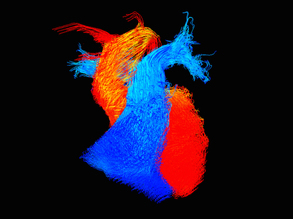

Flow Rider

British Heart Foundation 'Reflections of Research'